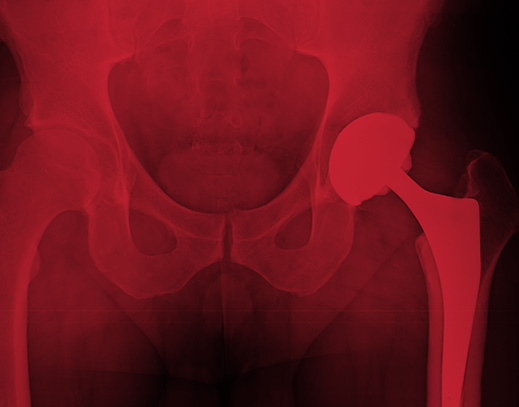

In Germany, around 220,000 patients undergo hip replacement surgery every year. Those who receive metal-on-metal hip replacements have experienced problems with bone loss that results in the need for painful and costly revision surgery. Researchers set about understanding why.

The scientists looked at tissues next to the hip implant, nearby bone marrow and joint fluids in the area. They wanted to see what changes could be caused by exposure to cobalt and chromium. They learned that dissolved metal ions penetrate the bone marrow, hindering mesenchymal stromal cells (MSCs) from forming the osteoblasts that generate bone growth. When researchers removed MSCs from the bone marrow of metal-on- metal hip implant patients, they saw that the MSCs could not differentiate into bone-forming osteoblasts. To confirm their findings, they took cell cultures from patients who had not received metal-on- metal hip replacements. The cell cultures were exposed to equivalent levels of dissolved cobalt and chromium and found that the results were identical. The researchers’ reported conclusion confirmed what Waters Kraus & Paul attorney Erin Wood has observed in her representation of those injured by metal-on-metal hip implants, like the Zimmer cup: The risks outweigh the benefits.